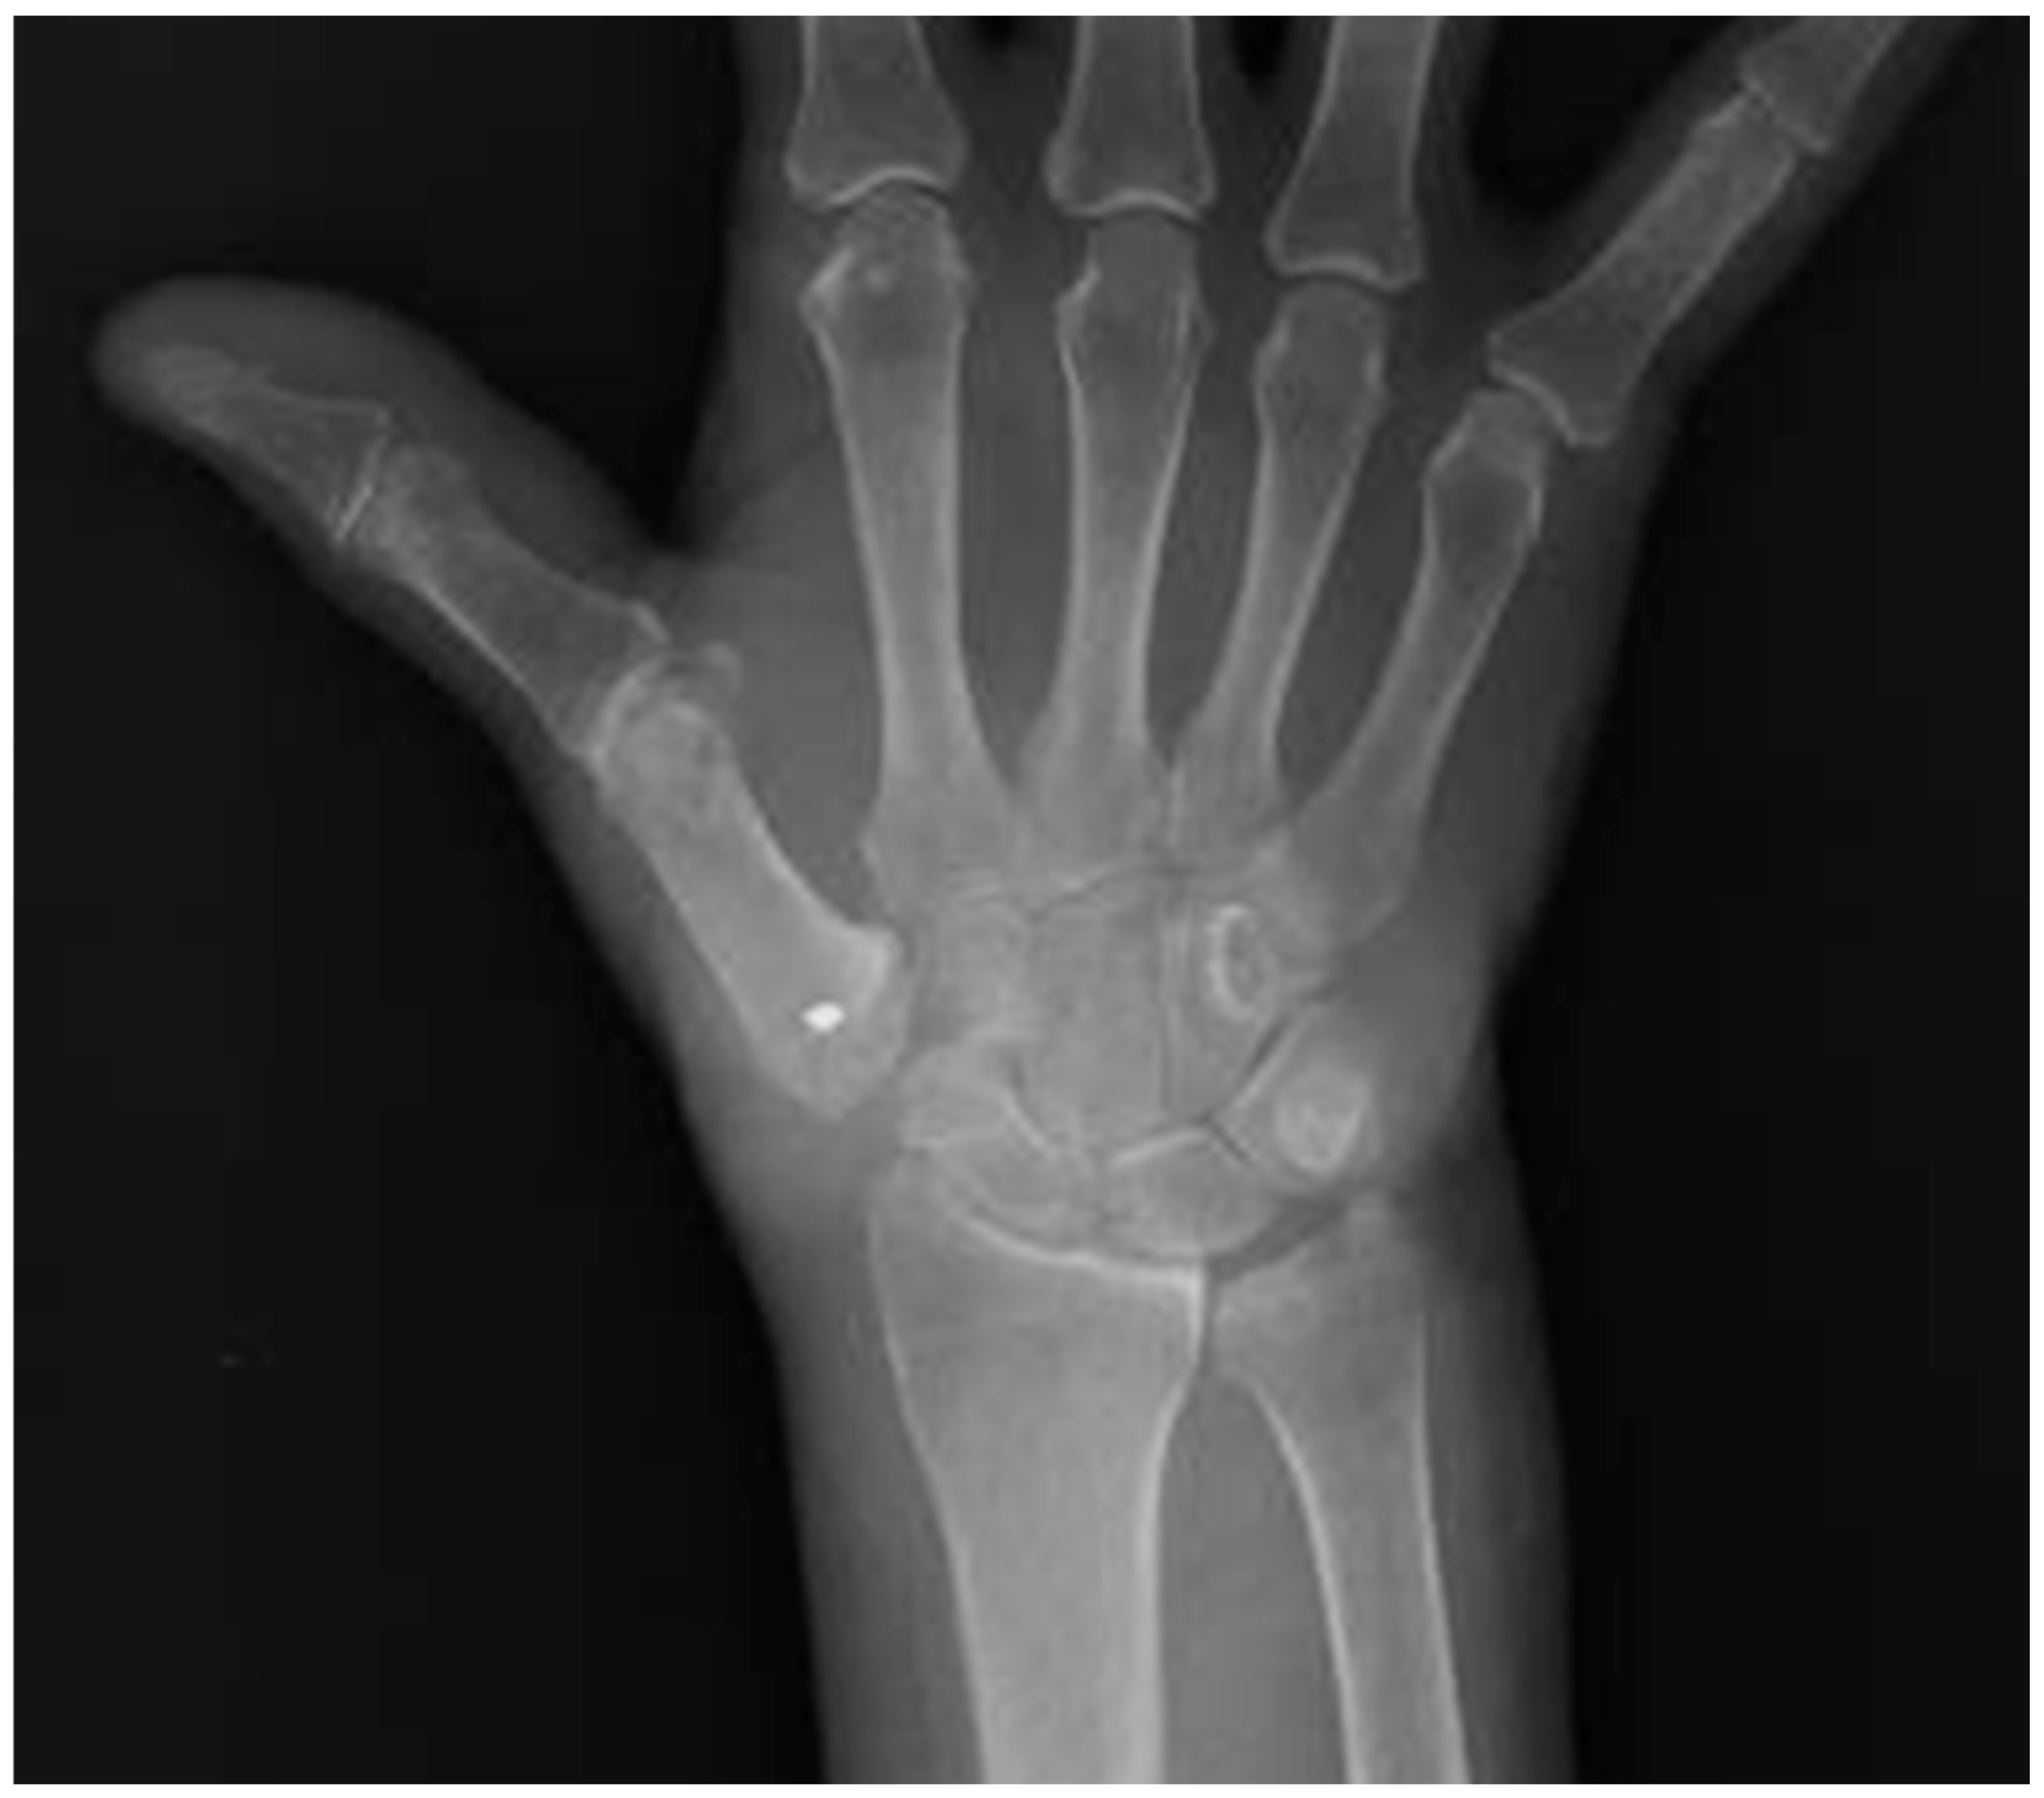

Figure 2. X-ray post-trapezectomy and tenoplasty in suspension (AST) with the flexor carpi radialis tendon fixed with a suture anchor at the base of the second metacarpal bone (Group A).